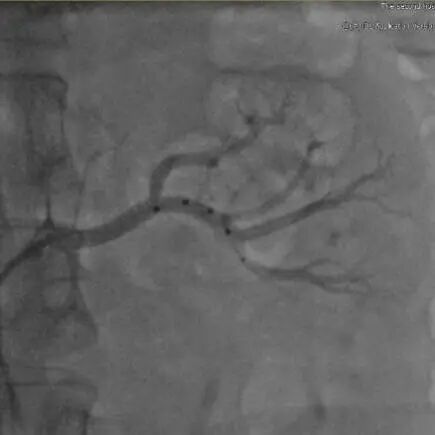

2.造影检查

冠脉造影

LCX中段90%狭窄

LAD弥漫粥样硬化

左侧肾动脉造影

左肾动脉未见明显狭窄

副肾动脉

右侧肾动脉造影

右肾动脉未见明显狭窄